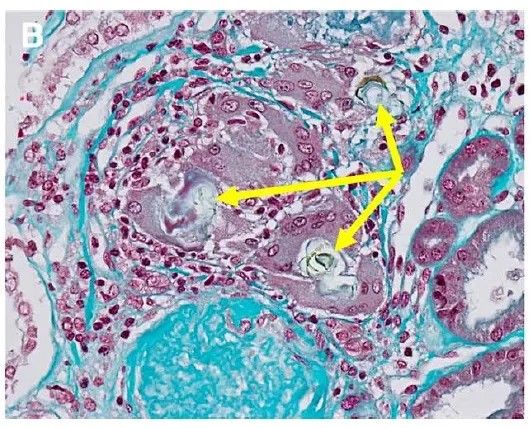

A glomerulonefrite por C3 (GNC3) resulta de ativação descontrolada da via alternativa do complemento e pode simular uma GN pós-infecciosa. O diagnóstico correto depende do reconhecimento do padrão de deposição de C3 e da investigação genética. Com terapias-alvo como o eculizumabe e o iptacopan, identificar precocemente a GNC3 pode mudar o desfecho do paciente.